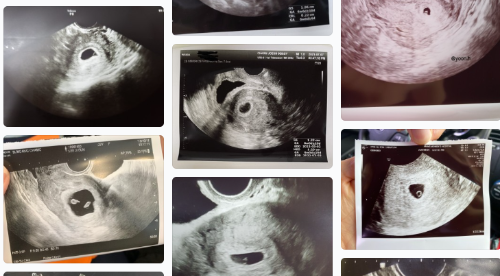

수정이 된 날로부터 5주차 정도가 되면 작은 아기집이 보일텐데요.

질초음파를 통해서 아기집, 모양, 크기, 위치 등을 살펴보면서

어떻게 자리를 잡았는지 병원에서 소식을 전해주실거랍니다.

아기집 난황 보이는 시기

임신 초기에는 아기집이 1~3mm로 아주 작아서 복부초음파로는 보기가 어렵습니다.

초기에 너무 일찍 병원에 간다면 피검사 이후 아기집이 보인다해도 난황, 심장을 확인하지 못하는 경우 역시 많답니다.